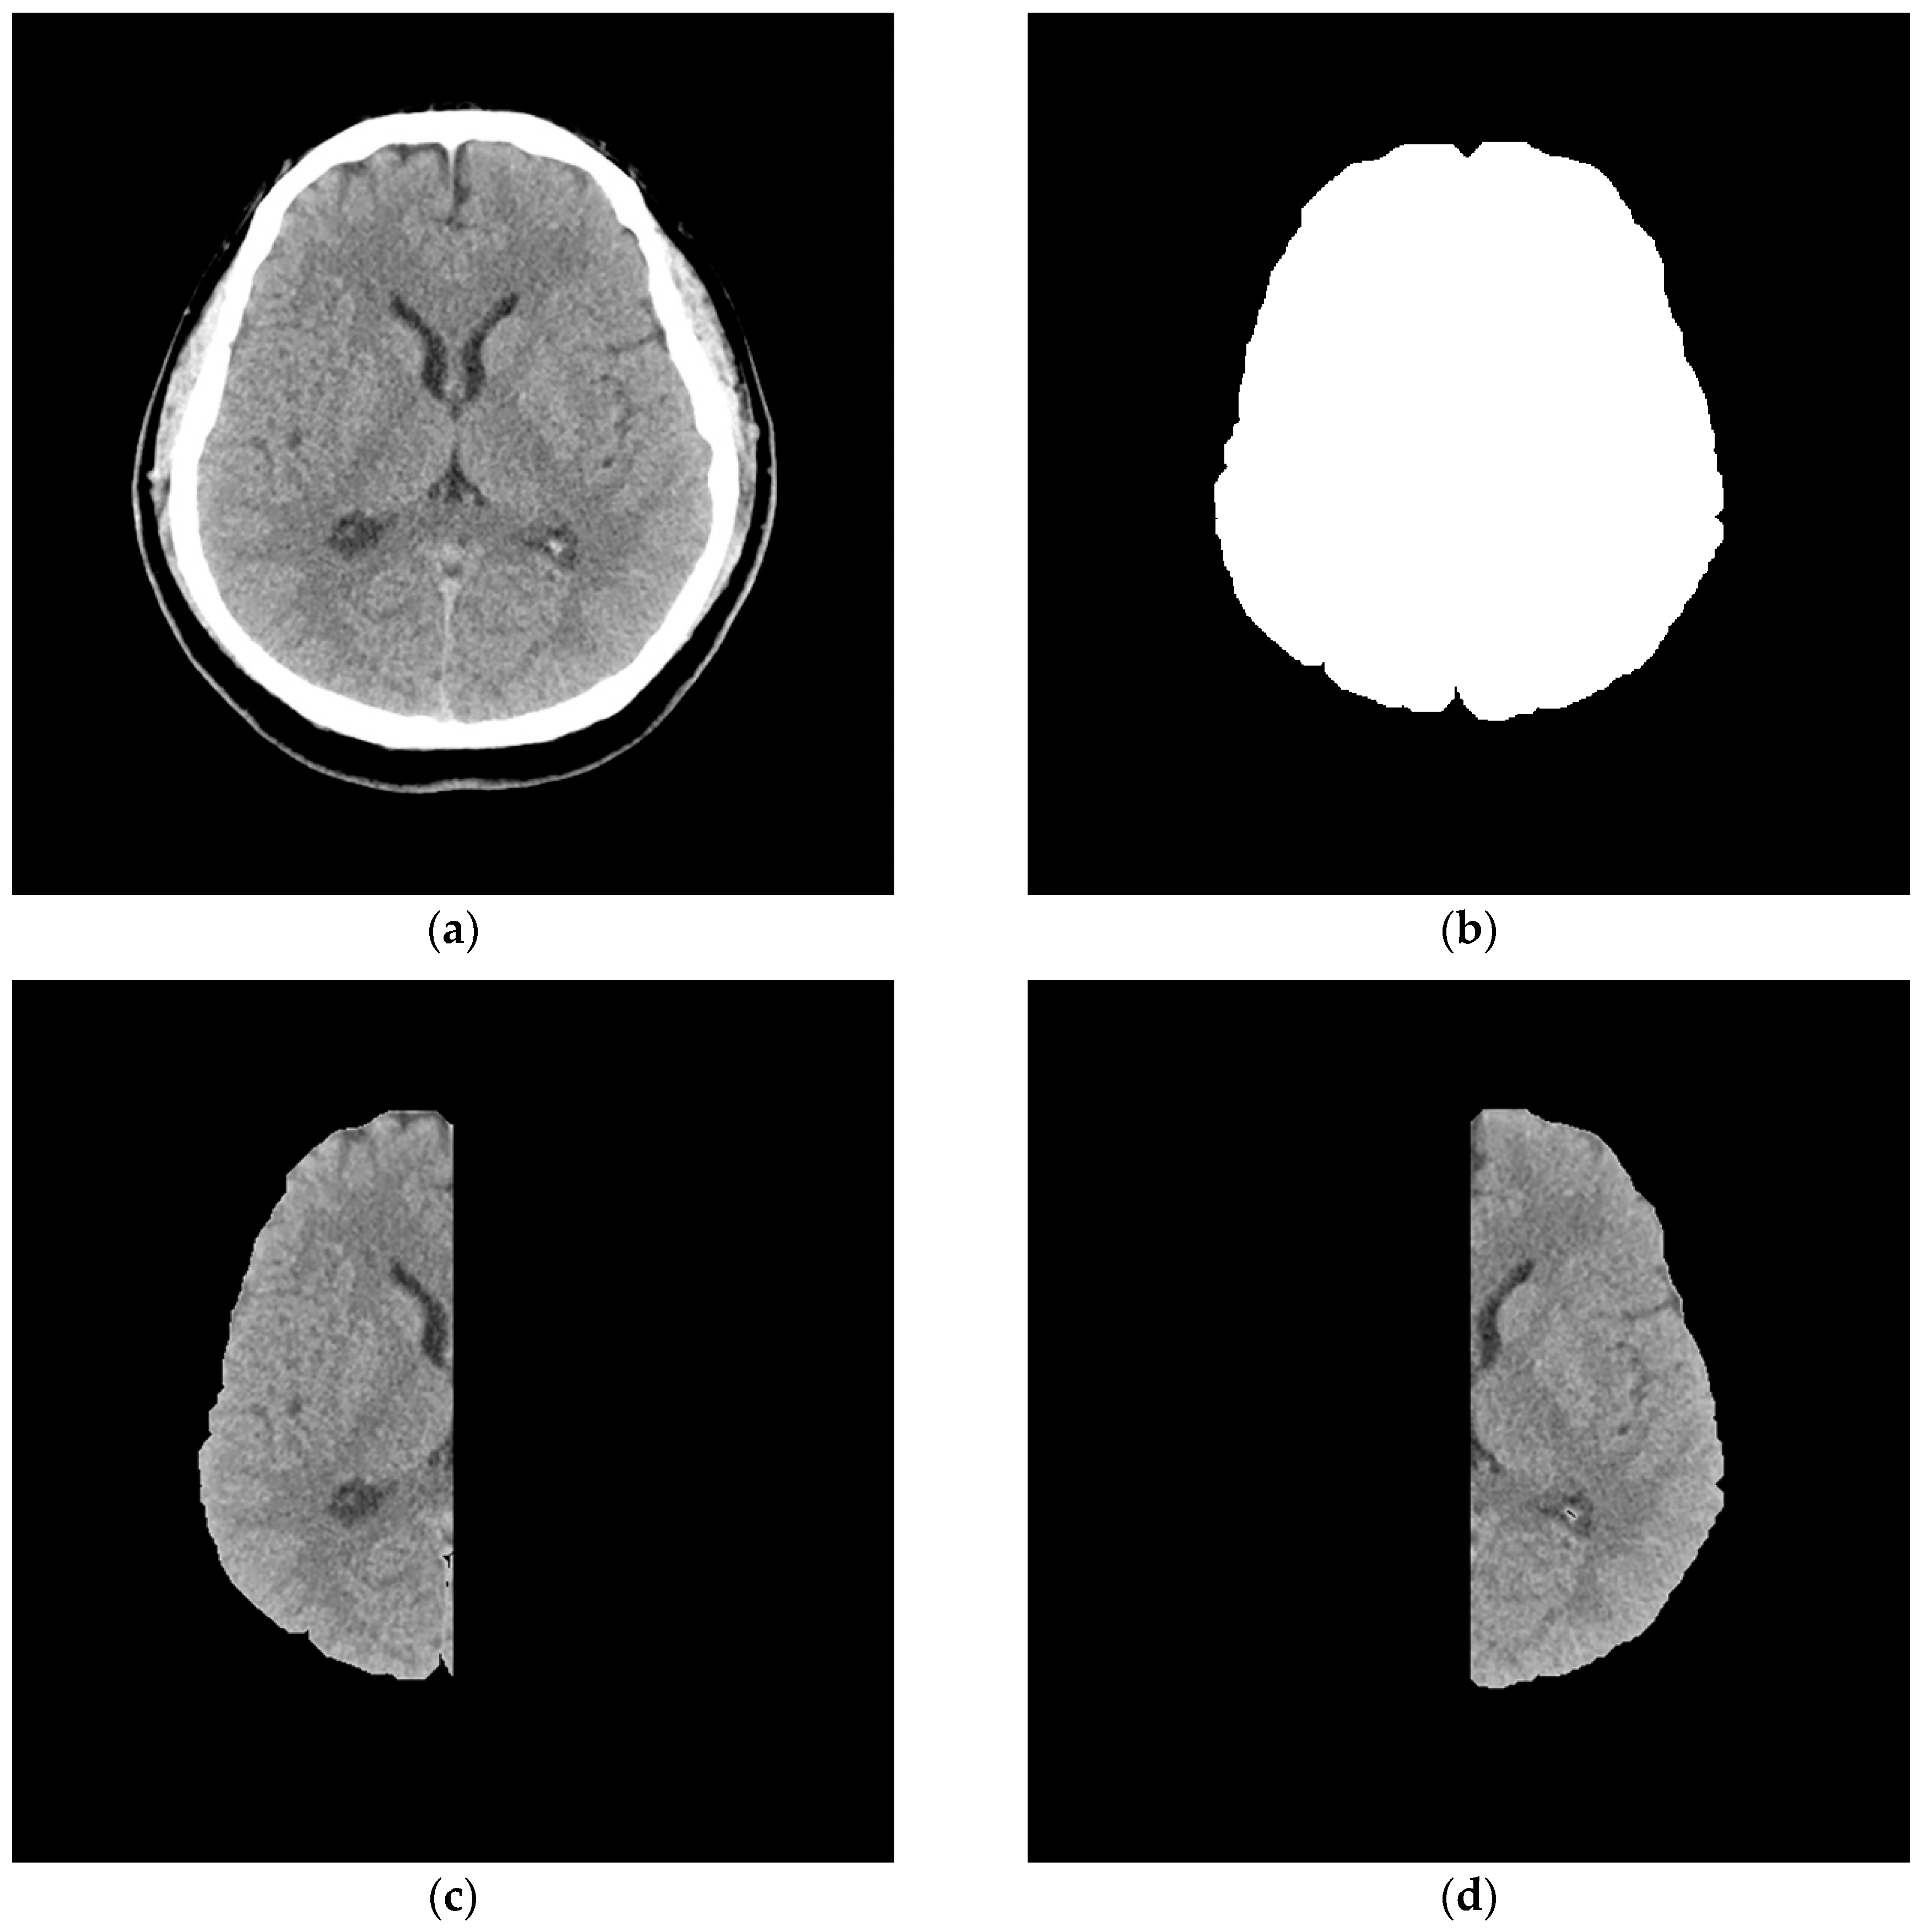

2. Materials and Methods

3. Stroke Pattern Extraction

3.1. Asymmetric Interpretation